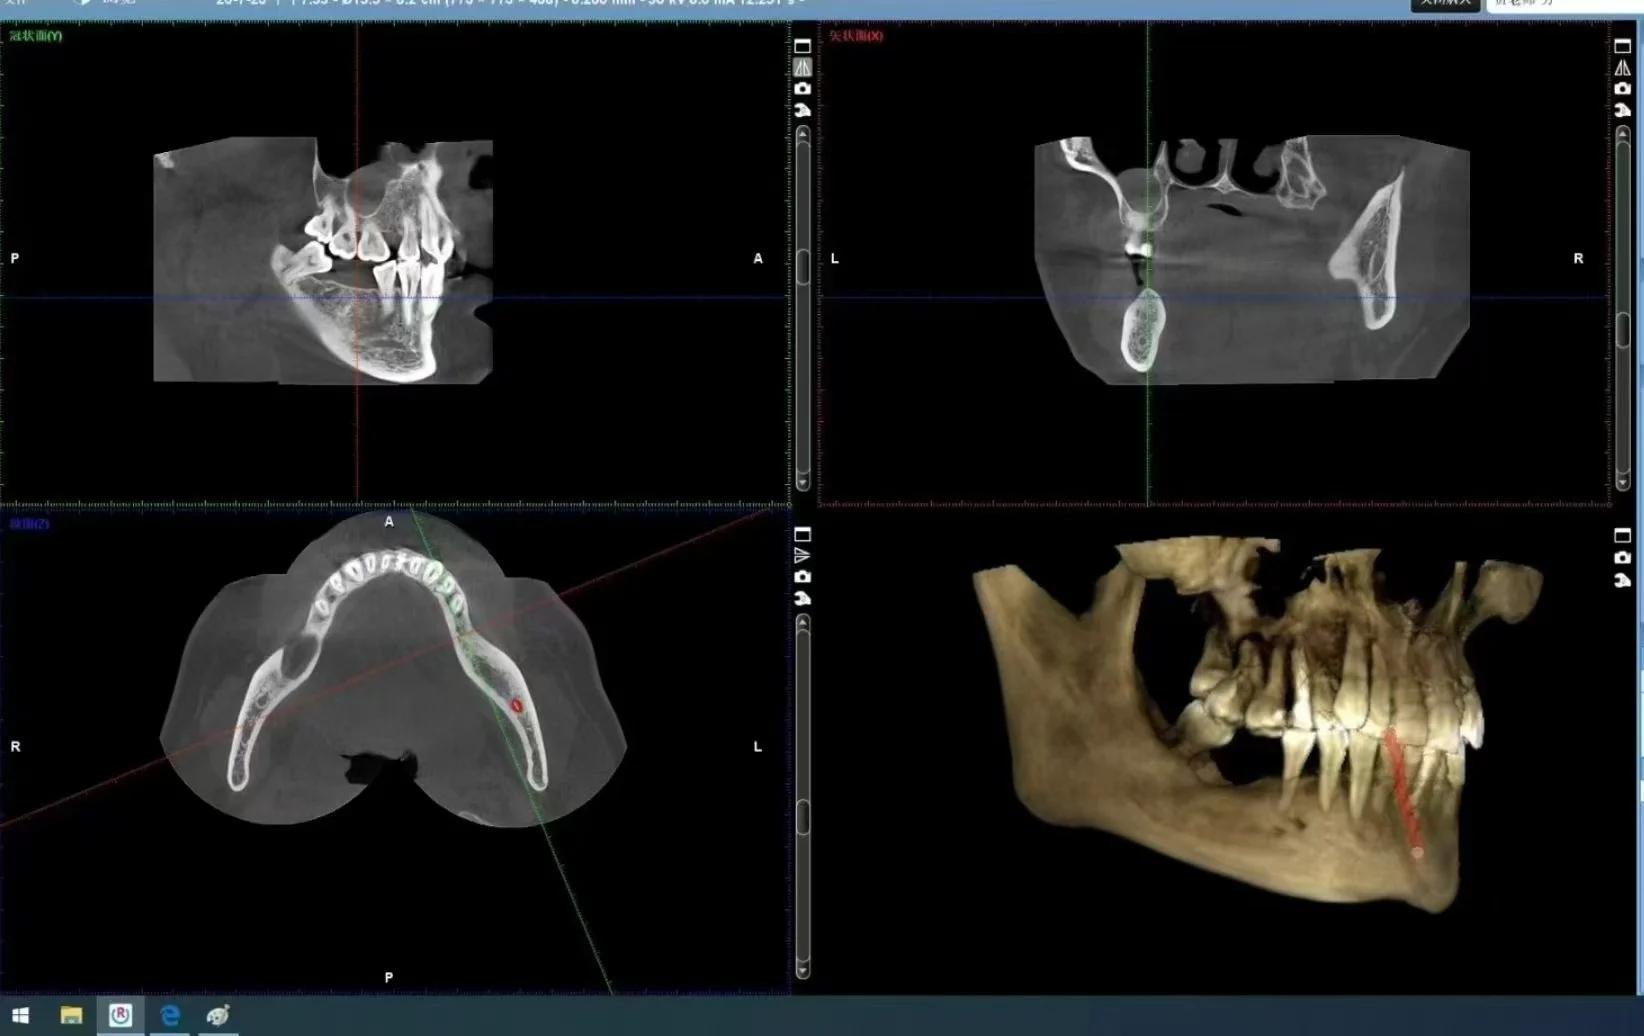

CBCT odontológico

Na fase de pré-diagnóstico, os dados faciais 3D do paciente foram obtidos por meio de digitalização facial, e a observação e eficiência do paciente foram comunicadas, e as comparações pré-operatórias e pós-operatórias foram imediatamente exibidas após o encaixe automático dos dados de digitalização oral, especialmente DSD e a apresentação dinâmica da ortodontia torna a comunicação do paciente médico mais simples e eficaz.Depois que o plano de tratamento for confirmado com o paciente, a varredura CT será tomada e instalada automaticamente quando houver necessidade de tratamento, e os dados de varredura de superfície serão

obtido.O encaixe automático de dados de digitalização oral e dados de tomografia computador permite que médicos e técnicos se comuniquem com Douguan com mais precisão e permite que os técnicos criem experiências médicas mais realistas por meio dos dados 3D reais do paciente, o esquema de design da situação é então publicado na impressora ou máquina de corte, para que tudo seja mais simples, preciso, mais satisfatório do paciente e melhor experiência